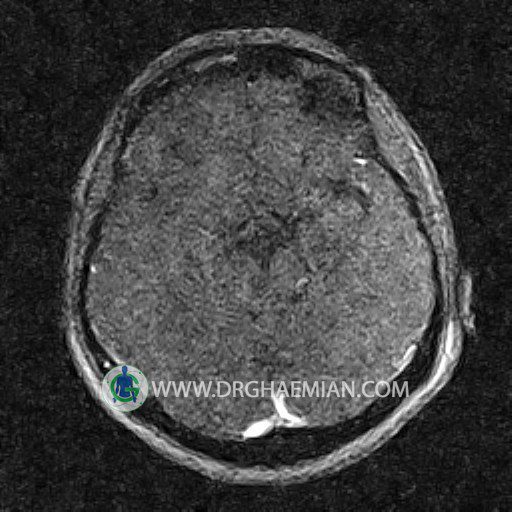

ام آر وی یک روش تصویربرداری دقیق و غیر تهاجمی است که برای معاینه ورید های بدن و ارزیابی سلامت رگ ها استفاده می شود. ورید ها خون را از اعضای بدن به قلب باز می گرداند تا دوباره اکسیژن و مواد مغذی به خون داده شود. ام آر وی جریان خون را ارزیابی و موارد غیرعادی مضر مانند لخته های خونی را شناسایی می کند. در این کیس ترومبوز دیواری مغز در سینوس عرضی راست و ترمبوز جزئی در سینوس عرضی چپ دیده می شود.

Images of the venous cranial vessels demonstrates a superior sagittal sinus of normal caliber with normal arrangement of draining superficial cerebral veins.

The great cerebral vein Galen inferior sagittal , straight sinus and left sigmoid sinus appear normal.

The right sigmoid sinus present a normal caliber.

The other evaluable deep cerebral veins , basal and labbe are normally developed and patent.

The other evaluable portions of the neurocranium show no abnormalities.

– Narrowing of left transverse sinus with filling defect & inthimal irregularity

suggestive for partial thrombosis

– Inthimal irregularity in anterior wall of right transverse sinus suggestive for mural thrombosis

are seen